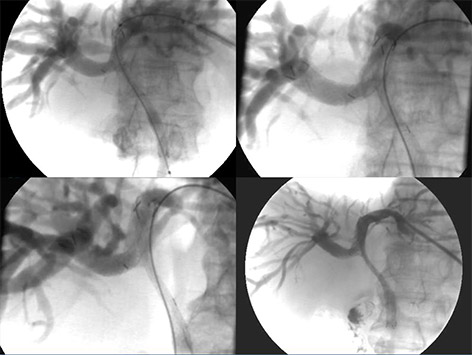

3. 간암화학색전술

카테터라는 미세한 관을 이용하여 인체의 혈관을 따라 들어가 암으로 직접 혈액을 공급하는 동맥을 찾고, 이를 통해

약을 투입하거나 혈관을 막아 암으로의 영양공급을 차단하여 암을 치료하는 방법으로서, 현재 간암의 치료에 가장 많이

시행되고 있습니다. 이는 전신마취와 개복술에 따르는 위험이 없고, 치료 후 회복되는 기간이 짧으며, 암의 숫자가 많거나,

전이되었거나, 간 기능이 나빠서 수술적 제거가 불가능한 경우에도 시술이 가능하다는 장점이 있습니다.